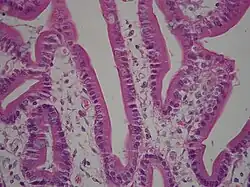

Histology

Under microscopy, the duodenum has a villous mucosa. This is distinct from the mucosa of the pylorus, which directly joins the duodenum. Like other structures of the gastrointestinal tract, the duodenum has a mucosa, submucosa, muscularis externa, and adventitia. Glands line the duodenum, known as Brunner's glands, which secrete mucus and bicarbonate in order to neutralise stomach acids. These are distinct glands not found in the ileum or jejunum, the other parts of the small intestine.[13]: 274–275

The villi of the duodenum have a leafy-looking appearance, which is a histologically identifiable structure. Brunner's glands, which secrete mucus, are only found in the duodenum. The duodenum wall consists of a very thin layer of cells that form the muscularis mucosae.